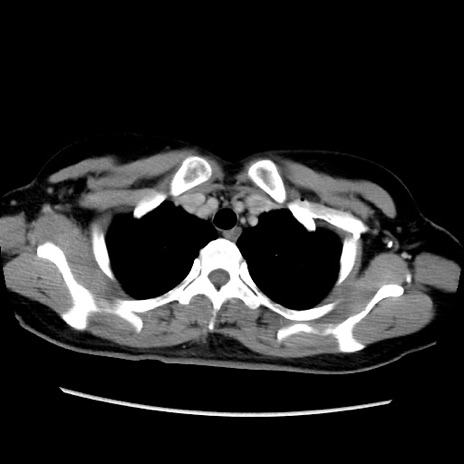

MRI(4日後)

【症例】40歳代女性

【主訴】上下腹部痛

【現病歴】2日目から下腹部痛あり。夜間は痛みで眠れなかった。昨日より上腹部痛と下痢が出現。臥位で痛みは軽快したため、休んでいた。本日になって臥位でも立位でも痛みが強くなってきたため救急要請。

【既往歴】子宮内膜症

【身体所見】部:平坦・軟、左上下腹部に圧痛あり、反跳痛あり。

【データ】WBC 21800、CRP 26.78